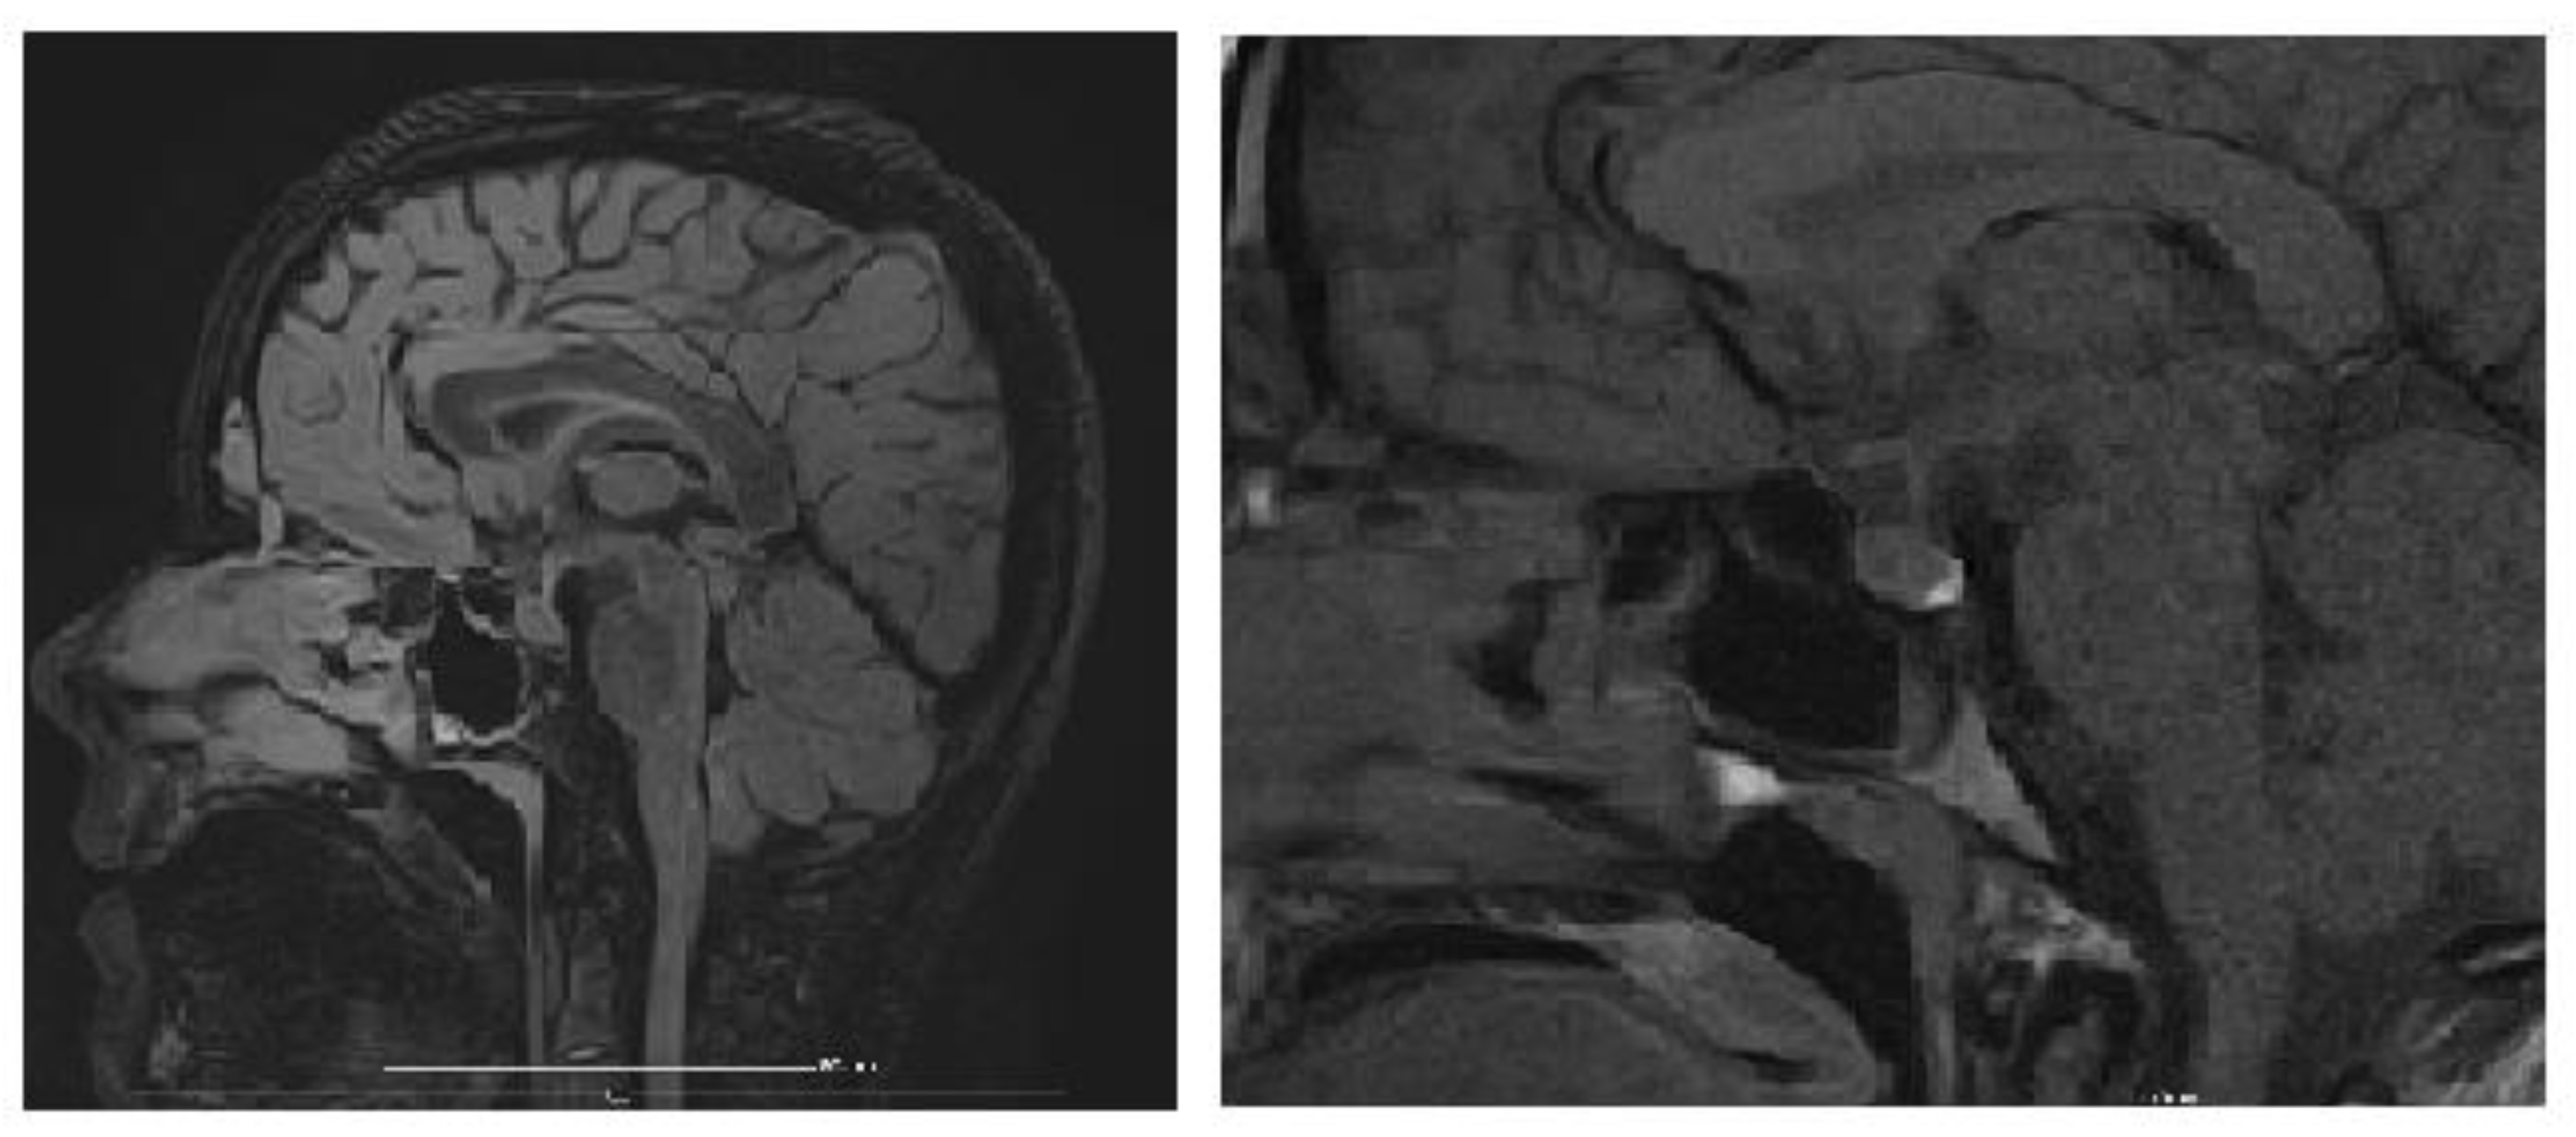

An MRI of the brain and pituitary gland was performed, revealing a pituitary microadenoma (Figure 3), most likely an incidental finding, ruling out other CNS pathologies that would explain chronic hyponatremia (tumor, trauma, vascular acquired conditions, or malformations). The dynamic post-contrast sequence shows a small 3 × 2 mm area with delayed enhancement in the adenohypophysis, considered unrelated to the patient’s symptoms, as pituitary hormone levels were normal, suggesting an incidentaloma.

Figure 3. Brain MRI (dynamic post-contrast sequence) showing a 3 × 2 mm pituitary microadenoma.